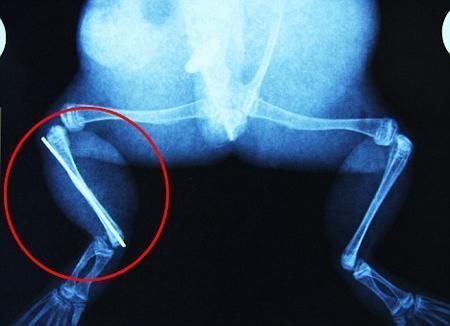

環(huán)球網(wǎng)4月2日?qǐng)?bào)道 據(jù)《每日郵報(bào)》報(bào)道,上個(gè)月,南非大牛蛙布魯萊的右小腿被鄰居家的一只狗咬到,導(dǎo)致粉碎性骨折,現(xiàn)在經(jīng)過(guò)2個(gè)小時(shí)的手術(shù),它的斷腿已經(jīng)被接上,它也因此成為有史以來(lái)第一只通過(guò)外科手術(shù)用鋼針接上斷腿的青蛙。

野生生物專家安妮經(jīng)常為學(xué)校寫教材,她認(rèn)為這是人類第一次通過(guò)手術(shù)給一只青蛙接斷腿。在手術(shù)開(kāi)始階段,獸醫(yī)把少量給狗用的麻醉藥注入到這只青蛙體內(nèi),讓它失去知覺(jué)。然后他在布魯萊的斷腿上切開(kāi)一個(gè)小口,把一根小鋼針植入腿里。最后獸醫(yī)給它縫了9針,把切口縫合在一起。僅僅幾周后,布魯萊就能在安妮家附近活動(dòng)了。這只青蛙大約已有25歲,主要以嚙齒動(dòng)物、蛇和其他青蛙為食。布魯萊所屬的牛蛙種群正在不斷減小,目前只能在非洲南部的濕地里才能看到這種青蛙。

安妮有2個(gè)孩子,她已經(jīng)從事20多年兩棲動(dòng)物保護(hù)工作。她認(rèn)為鄰居家的狗狗在把布魯萊從地下刨出來(lái)的時(shí)候,它正在地下冬眠、她說(shuō):“世界上只有這個(gè)地區(qū)能看到這種牛蛙,這種青蛙現(xiàn)在變得越來(lái)越稀少。因?yàn)槲覐氖乱吧锉Wo(hù)工作,因此認(rèn)識(shí)很多兩棲動(dòng)物專家,但是以前他們誰(shuí)也沒(méi)見(jiàn)過(guò)這種事情?吹讲剪斎R越來(lái)越健康我非常開(kāi)心。現(xiàn)在還需要一段時(shí)間,它的金屬腿和它的骨骼才能融為一體,那時(shí)布魯萊會(huì)跟以前一樣健康。我們認(rèn)為這個(gè)過(guò)程需要幾周時(shí)間,但是一旦它完全康復(fù),我希望把它放歸大自然,讓它重新回到它最鐘愛(ài)的濕地里。”